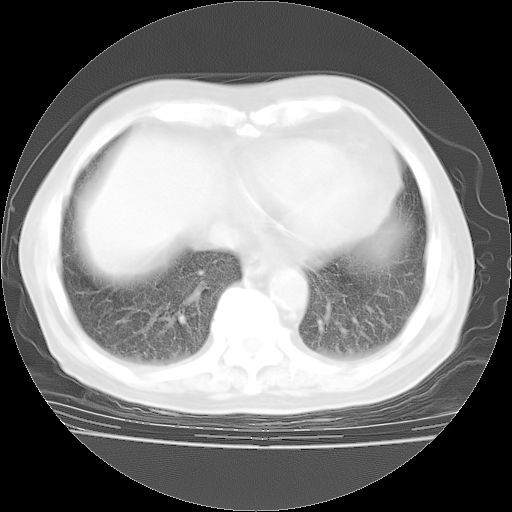

4月28日肺部CT——再次出现类似去年5月9日——透光度降低,“间质性”改变。

4月28日肺部CT——再次出现类似去年5月9日——磨玻璃样、间有“粟粒样”改变。

个人阅读4.14日肺部CT平扫:纵隔窗无异常,但肺窗示:双下肺内、后基底段有片絮状侵润影,部位以后基底段为著,以间质改变为主,呈急性肺泡炎征像,和首次住院影像学有相似之处。仅是个人读片,明日请相关专家再读片哈。其它建议同上。

1、108#的是4月14日的胸部CT(发此贴时还没看着28日的CT)。14日的胸部CT其实已经出现改变(如108#所述),个人认为28日的胸部CT除纵膈窗疑似有双侧胸膜增厚或少量胸积液(可行胸部B超明确)外,与4月14日对照病变有所加重;2、已经给予“异烟肼、利福平、乙胺丁醇”抗痨治疗?如果是,甲强龙80mg可缓慢减量;如果环磷酰胺已停用,暂不使用;3、中性粒细胞92%,明显升高,目前体温情况?注意合并细菌感染可能,使用左氧氟沙星情况下,是否联用B-内酰胺类抗菌药物?另外是查免疫全套非风湿全套。

今请临免主任会诊后认为:4月14日胸部CT已有双下肺间质性改变。患者病情复发多系激素减量过快不正规所致。目前甲强龙80mg/日,一周后酌情开始减量,不易过快。环磷酰胺若已停用,暂不使用。他同意目前抗菌药物使用,但应考虑是否加用B-内酰胺类抗菌药物(中性细胞明显增高);2、结核复发目前依据不足;3、若免疫全套各项指标正常,考虑多系特发性肺间质炎可能大。4、加强支持,并注意保护胃黏膜。